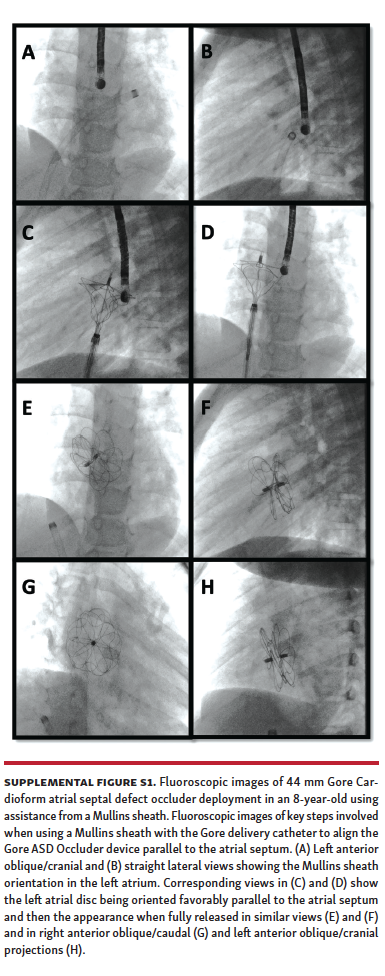

A total of 98 patients underwent attempted ASD closure during the study period (70 patients from the Gore ASSURED Clinical Study-Pivotal and Continued Access studies) and 28 patients after the study period. Of these patients, 52 underwent attempted secundum ASD closure using a long Mullins sheath (Supplemental Figures S1 and S2), while 46 patients underwent attempted secundum ASD closure with the Gore Cardioform delivery catheter through a short sheath in standard fashion.

Mullins-sheath facilitated Gore Cardioform ASD occluder delivery technique. The mechanism of favorable exaggeration of the angle of the Gore Cardioform ASD occluder delivery system when used with a Mullins sheath is seen in Figure 1. In large defects or in defects with deficient rims, the angulation of the Gore delivery catheter may not allow for alignment of the device parallel to the atrial septum, with resultant device prolapse superiorly through the defect into the right atrium (Figure 2). In such situations, the short sheath was exchanged for an appropriately sized 63 cm-long or 75 cm-long Mullins sheath in the left atrium and the dilator and wire were removed (same Fr size as required short sheath Fr size). When used in combination with a Mullins sheath, the angulation is exaggerated enough to facilitate better alignment parallel to the atrial septum (Figure 3). The Mullins sheath was rotated clockwise to assume a posterior orientation to align the device parallel to the atrial septum as it was being delivered. The Gore Cardioform ASD occluder delivery catheter was then advanced through the Mullins sheath, which was positioned with continuous clockwise rotation, often by the assistant, as the primary operator deployed the device. In some cases, despite this maneuver, the device was not aligned parallel to the atrial septum. In such cases, once the left atrial side of the device was deployed and aligned in the best possible way, the Mullins sheath was withdrawn (if 63 cm-long sheath was used) to the inferior vena cava or right atrium to serve as a “fixed point,” whereby further clockwise rotation of the Gore delivery catheter could be performed if needed to facilitate further device alignment as parallel to the atrial septum as possible (Figure 4). In some cases, the Gore delivery catheter was rotated 180° clockwise despite the use of the Mullins sheath to facilitate capture of the aortic and superior vena cava rims. Use of the Mullins sheath also facilitated delivery of the device when inferior disc prolapse into the left atrium was encountered (Figure 5). Finally, in some cases, the tip of the Gore Cardioform ASD occluder delivery catheter was also hand-shaped to further exaggerate its angle. The use of the Mullins sheath was at the discretion of the implanting physician.